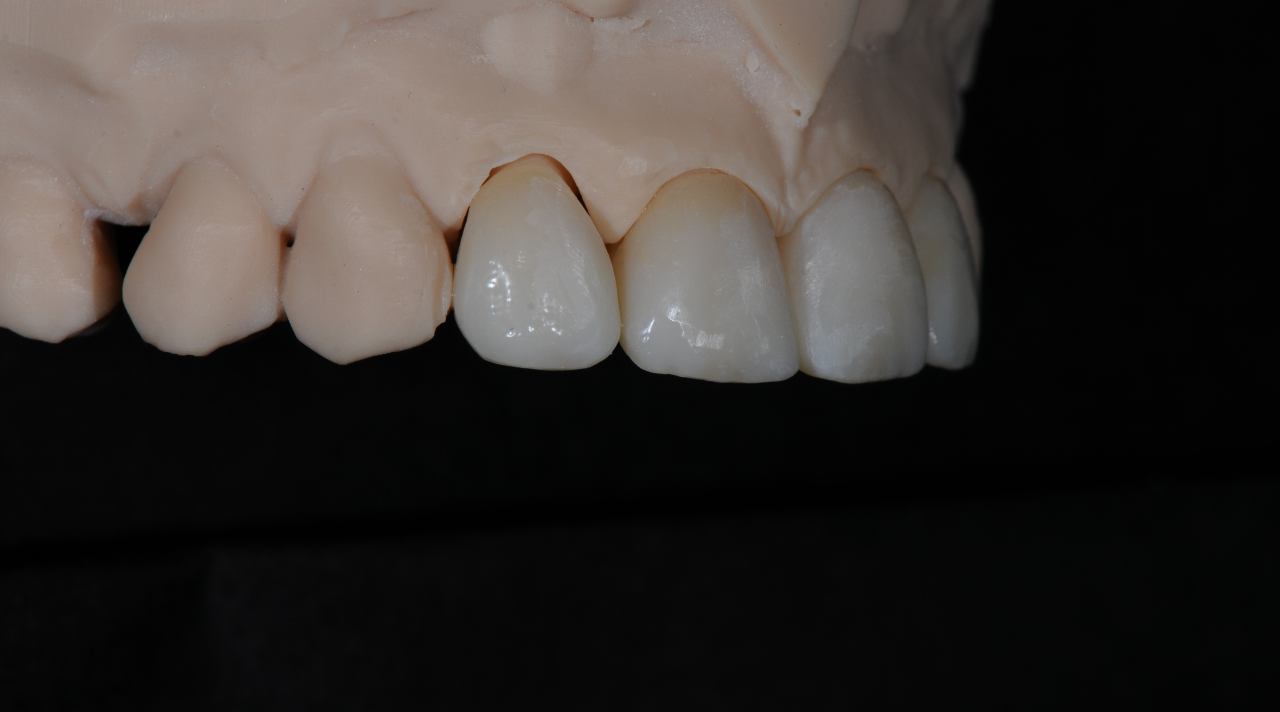

LJUSKICE

Keramičke ljuskice (veneers) predstavljaju idealno rješenje za estetske korekcije prednjih zuba. Može se korigirati oblik zuba, boja, veličina i sitne nepravilnosti u položaju.

Ljuskice se izrađuju potpuno individualizirano, uz pomoć digitalne tehnologije i u vlastitom laboratoriju. Za dodatne informacije ili dogovor oko termina nazovite ili pošaljite upit

Krunice

Zubne krunice izrađuju se digitalno, uz korištenje modernih materijala poput cirkona i keramike. Svaka krunica je izrađena po mjeri u vlastitom laboratoriju, čime se znatno smanjuje vrijeme čekanja.

Smile design

Digitalno planiranje novog osmjeha. Unaprijed se kompjuterski određuje oblik, boja, dužina zuba te definitivni izgled pacijenta.